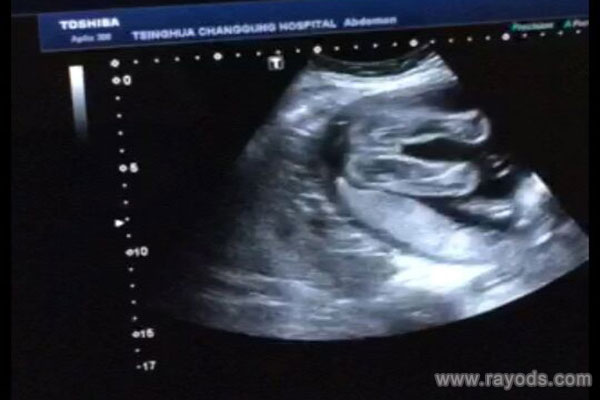

而对于怀孕上脉早这个说法其实和怀孕上身早是一个道理,继而不少人就总结出了,上身早或者上脉早的都是男孩,其实这个说法是行不通的,其实不管是怀的男孩还是女孩,都存在上身或者上脉早或者晚的。说回来不管是怀男孩还是怀女孩,其几率都是一样的。也有宝妈说这个说法是不能够知道胎儿性别的,只有等孕周大一些了之后做B超检查才会知道。

@回忆也是幸福:其实你根据这些情况来判断,宝宝的性别都是不太准确的,没有一些科学依据,你如果比较好奇,在20周以后可以做个b超检查,应该可以清楚地看到。

@欣欣妈:最准还是B超检查吧,我都套了好多症状了,一般怀孕3个月后做B超检查是可以看出男女孩的。